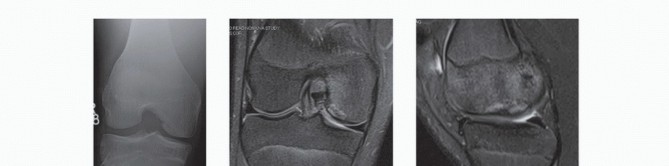

AVN most commonly is seen in the hip. The knee is the second most common location but accounts for only about 10% as many cases as the hip. AVN can affect the femur, tibia, or both; is bilateral in over 80% of cases; and usually involves multiple condyles (

FIG 3A

).

AVN involves a larger area of subchondral bone, with extension into the epiphysis and even the metaphysis or diaphysis.

Spontaneous osteonecrosis of the knee is different from AVN. Spontaneous osteonecrosis of the knee occurs in patients older than 55 years, involves only one condyle (most commonly medial), and is unilateral in 99% of cases (

FIG 3B,C

FIG 3 • A. MRI scan of AVN involving multiple condyles with extension into the metaphysis. B,C. MRI scans of spontaneous osteonecrosis of the knee involving the medial condyle only. Note the edema adjacent to the involved area.